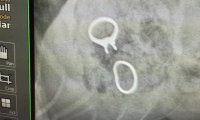

Щенок лабрадора из американского города Талса попал на операционный стол. Причиной этого стали проглоченные кольца хозяйки, стоимостью 23 тысячи долларов.